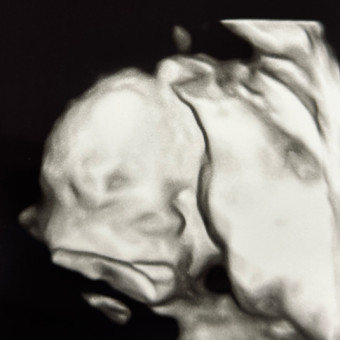

hannah, alec & baby rosemary 🤍Feeding